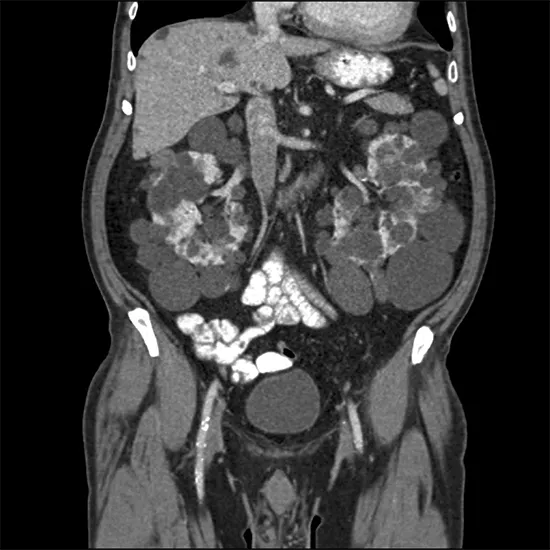

CECT (Contrast Enhanced Computerized Tomography) Whole Abdomen Test

CECT Whole abdomen is a diagnostic imaging tool that produces detailed images of internal organs, bones, soft tissue, and blood vessels. Intravenous contrast dye is injected into the body during this test to provide a more detailed view of the blood vessels. It also aids in the diagnosis of biliary system problems (liver, pancreas, gallbladder, etc.).

CECT scanning is frequently regarded as the most effective method for diagnosing abdominal pain, suspected cancer, kidney or gall bladder stones, and infections. It also aids in the evaluation of any illness's treatment progress.